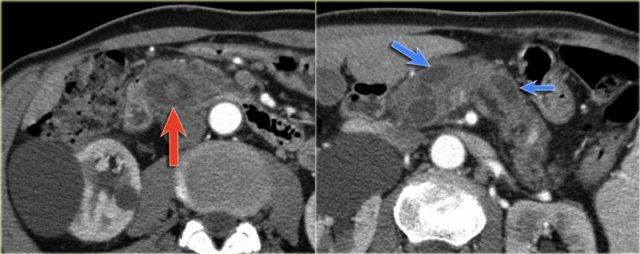

Hình ảnh CT của một IPMN với ống tụy giãn (mũi tên xanh).

Lưu ý nốt đặc có ngấm thuốc tại đầu tụy (mũi tên đỏ).

Tiếp tục xem hình ảnh siêu âm.

Hình ảnh siêu âm cho thấy thành phần ống nhánh kích thước lớn nằm trong đầu tụy.